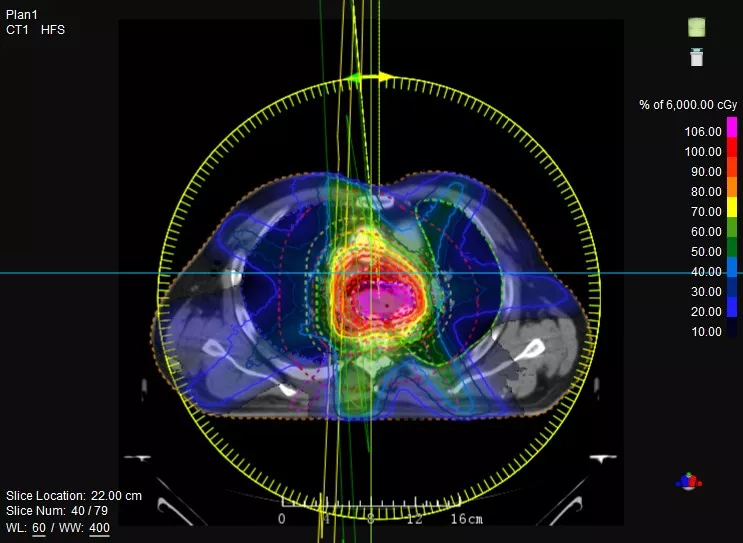

機(jī)載CT影像可直接用于放療計(jì)劃制作

鼻咽癌患者,進(jìn)行旋轉(zhuǎn)容積調(diào)強(qiáng)治療(uARC)

一體化CT-linac讓自適應(yīng)放療ART概念變?yōu)楝F(xiàn)實(shí)。患者全療程狀態(tài)監(jiān)控,適時(shí)在線調(diào)整治療計(jì)劃,精準(zhǔn)控制治療劑量,為患者動(dòng)態(tài)定制個(gè)體化治療方案。uAI賦能智能勾畫和自動(dòng)計(jì)劃,秒級(jí)勾勒靶區(qū)和危及器官,大幅縮短自適應(yīng)放療時(shí)間。

聯(lián)影CT-linac全程監(jiān)測治療過程病灶的變化,及時(shí)調(diào)整和優(yōu)化治療方案